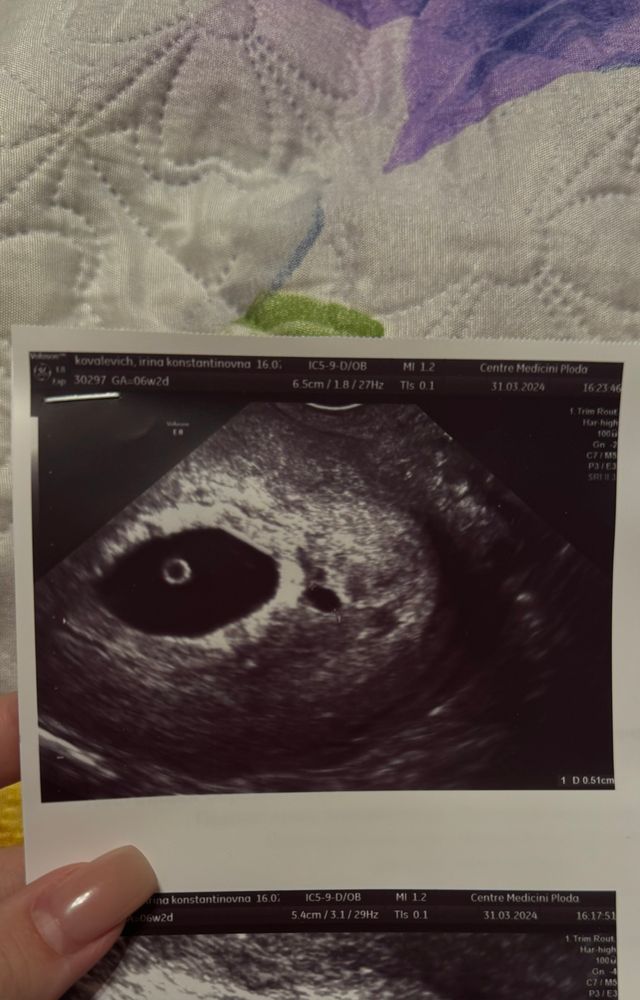

Второе плодное яйцо?

Была два раза на УЗИ, на двух сказали, что второе плодное яйцо под вопросом

одно плодное яйцо четко визуализируется, есть эмбрион, увидели только сегодня

второе плодное яйцо под ?, по размерам меньше первого

Киста в полости матки?))) на снимке прям четкое второе плодное яйцо, к сожалению, скорее всего не разовьется. Поздравляю с беременностью, желаю легко выносить🌺